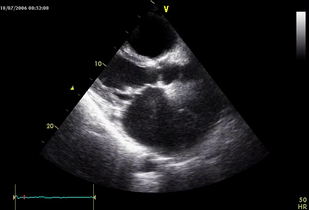

• Обложка: Ревматический умеренный митральный стеноз (рис. 7.3)